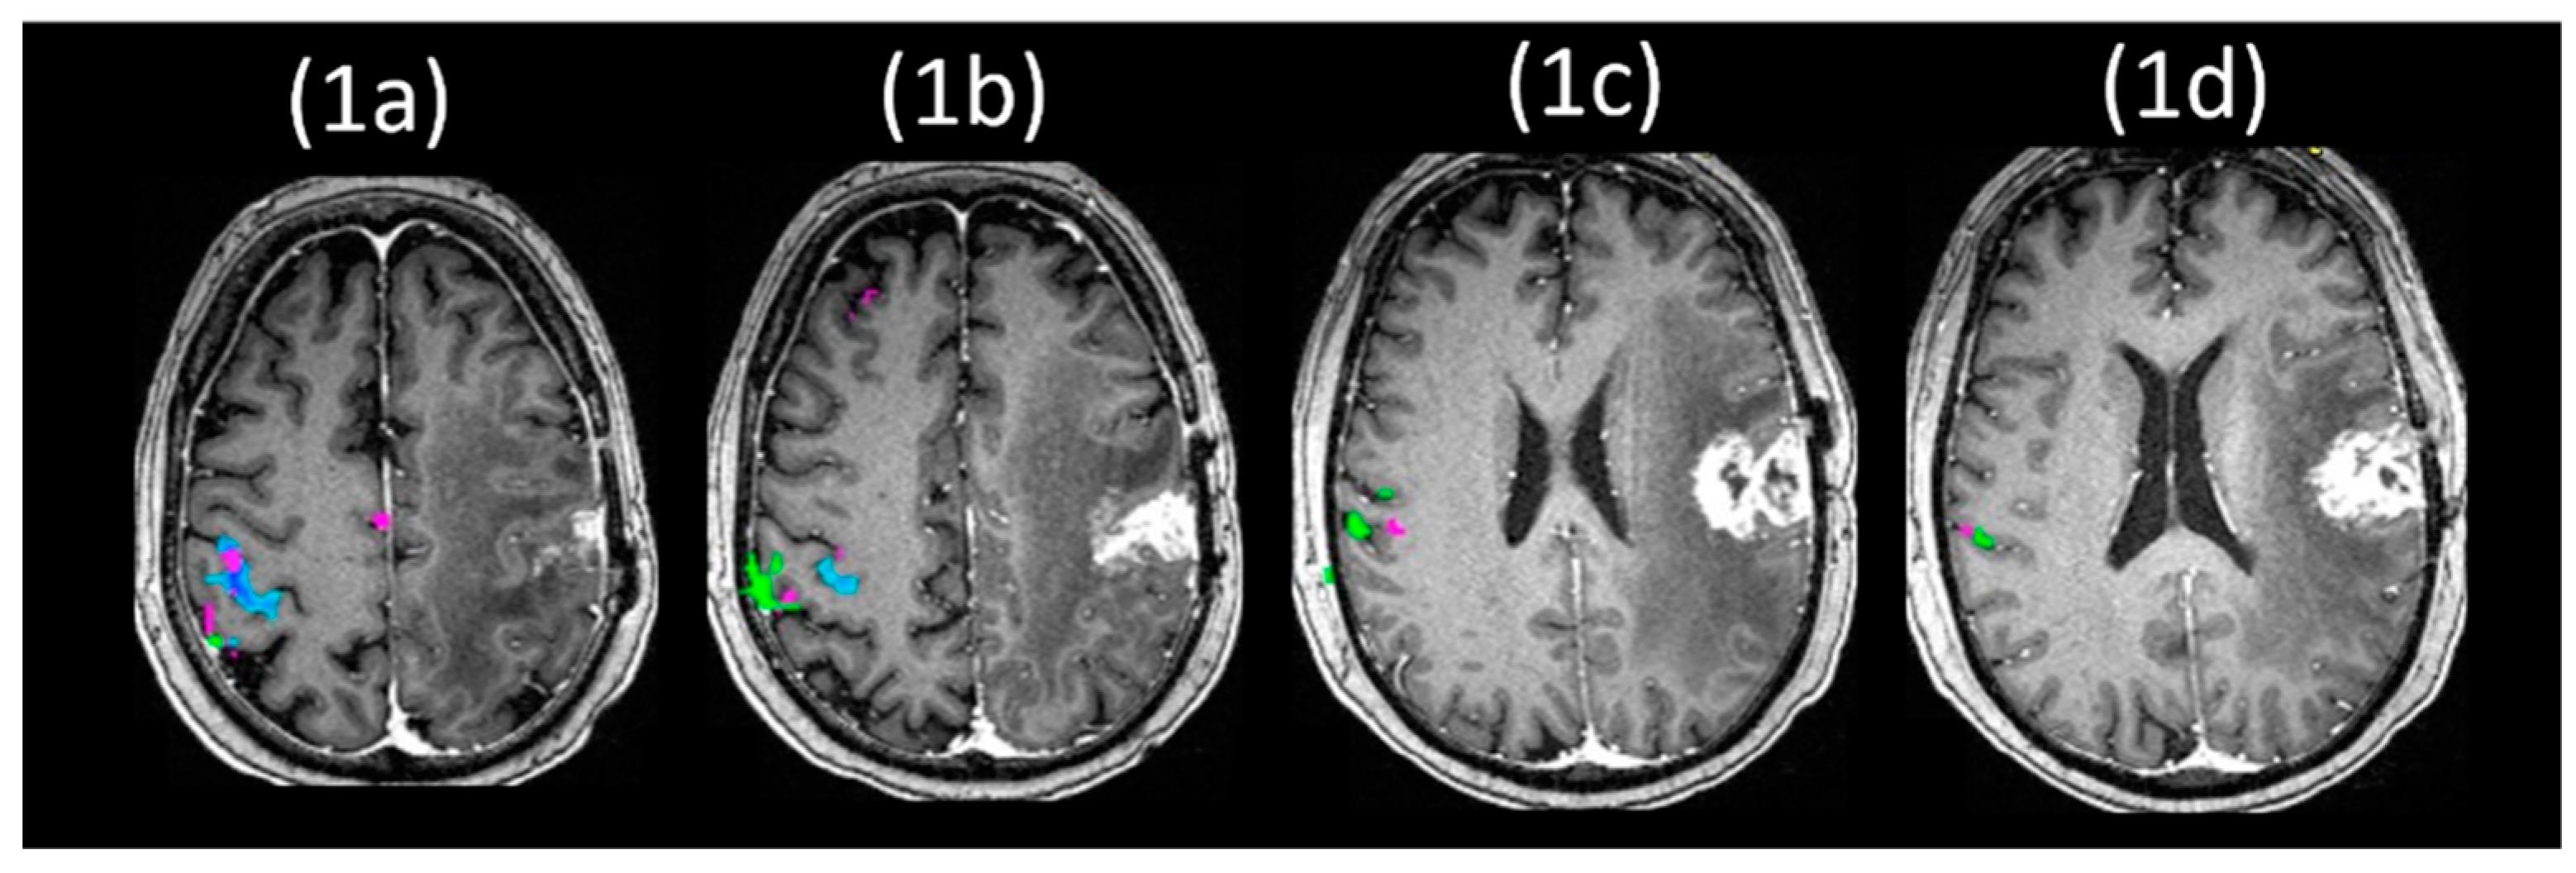

- Agarwal, S.; Lu, H.; Pillai, J.J. Value of Frequency Domain Resting-State Functional Magnetic Resonance Imaging Metrics Amplitude of Low-Frequency Fluctuation and Fractional Amplitude of Low-Frequency Fluctuation in the Assessment of Brain Tumor-Induced Neurovascular Uncoupling. Brain Connect. 2017, 7, 382–389. [Google Scholar] [CrossRef] [PubMed]

- Agarwal, S.; Sair, H.I.; Airan, R.; Hua, J.; Jones, C.K.; Heo, H.Y.; Olivi, A.; Lindquist, M.A.; Pekar, J.J.; Pillai, J.J. Demonstration of Brain Tumor-Induced Neurovascular Uncoupling in Resting-State fMRI at Ultrahigh Field. Brain Connect. 2016, 6, 267–272. [Google Scholar] [CrossRef] [PubMed]

- Agarwal, S.; Sair, H.I.; Gujar, S.; Hua, J.; Lu, H.; Pillai, J.J. Functional Magnetic Resonance Imaging Activation Optimization in the Setting of Brain Tumor-Induced Neurovascular Uncoupling Using Resting-State Blood Oxygen Level-Dependent Amplitude of Low Frequency Fluctuations. Brain Connect. 2019, 9, 241–250. [Google Scholar] [CrossRef]

- Agarwal, S.; Sair, H.I.; Yahyavi-Firouz-Abadi, N.; Airan, R.; Pillai, J.J. Neurovascular uncoupling in resting state fMRI demonstrated in patients with primary brain gliomas. J. Magn. Reson. Imaging 2016, 43, 620–626. [Google Scholar] [CrossRef]